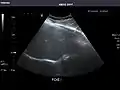

Kidneys: Right and left kidneys measure 11.5 cm and 12 cm in length respectively. No hydronephrosis. Small left lower pole kidney cyst.

Left kidney